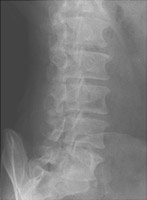

Spondylolysis refers to failure of fusion of the pars interarticularis, most often at the lower lumbar spine. This is usually a congenital defect, although it may occasionally be post-traumatic. The process may affect one or both sides of the spine. Oblique radiographs are best for the detection of this abnormality.

- Click on the image for a larger versionAOblique radiograph of the lumbar spine. This shows a pars defect.